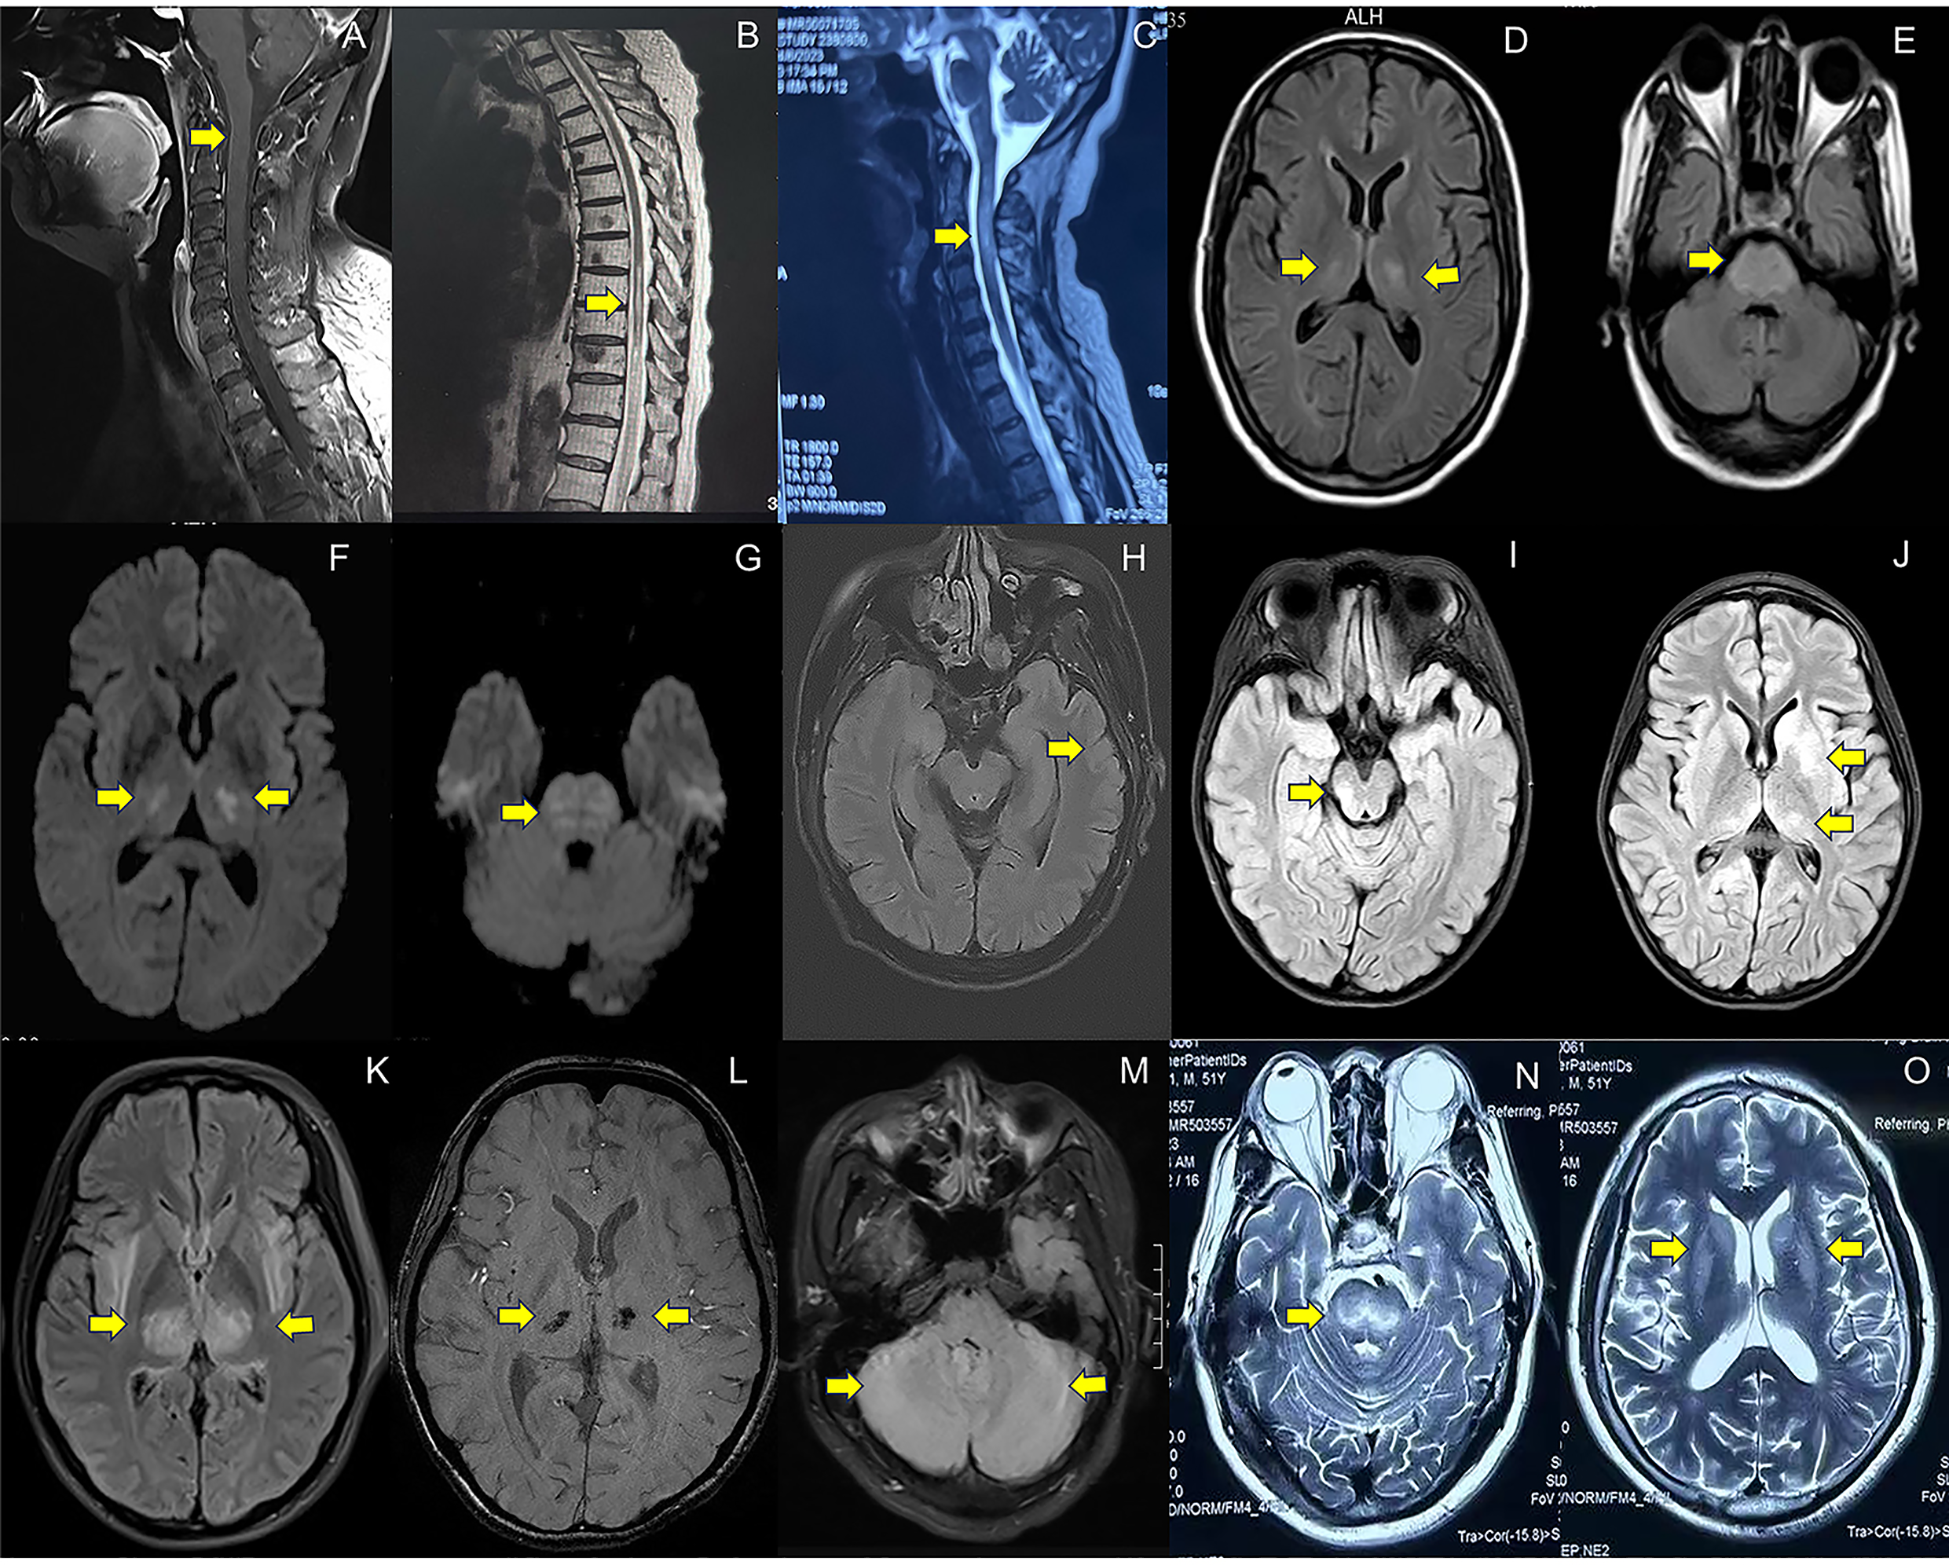

Figure 2

MRI imaging in patients with neurological complications associated with COVID-19. (A). Abnormal enhancement of the cervical spinal cord meninges on T1-weighted imaging with contrast enhanced sequences (case 9, spinal meningitis); (B). Longitudinally extensive hyperintensity lesions at T8-L2 level on T2WI(case 17, myelitis); (C). Longitudinally extensive hyperintensity lesions at C1-6 level on T2-weighted imaging(T2WI) (case 1, neuromyelitis optica spectrum disorders); (D–G). Symmetrical hyperintensity lesions in pons, bilateral hippocampus, thalamus, basal ganglia on Fluid-Attenuated Inversion Recovery (FLAIR) (D, E) and Diffusion-Weighted Imaging (DWI) (F, G) (case 39, other encephalopathy/encephalitis); (H). Gyrus-like hyperintensity lesions with swelling cortex in left temporal lobe on FLAIR (case 32, limbic encephalitis); (I, J). Hyperintensity lesions in pons, thalamus and basal ganglia on FLAIR (case 27, the overlapping syndrome of MOG-antibody disease and NMDAR encephalitis); (K, L). Hyperintensity lesions in bilateral thalamus on FLAIR (K) and susceptibility-weighted imaging(SWI) detect hemorrhages in bilateral thalamus (L) (case 48, acute necrotizing encephalopathy); (M). Hyperintensity lesions in bilateral cerebellum on FLAIR (case 52, cerebellitis); (N, O) Symmetrical hyperintensity lesions in bilateral basal ganglia and brainstem on T2WI (pontine and extrapontine myelinolysis). Detailed case information and numbers are available in the Supplementary Materials.

Spinal MRI was performed on all patients (16/16). Within the subgroup diagnosed with myelitis/spinal meningitis (11 cases), 27.3% (3/11) exhibited no detectable lesions in spinal cord on MRI. 18.2% (2/11) of cases demonstrated abnormal meningeal enhancement in the cervical spinal cord (Figure 2A) or conus medullaris. The majority (6/11) displayed T2WI hyperintensity lesions (Figure 2B), some with additional enhancement. For cases with NMOSD, MRI results consistently revealed longitudinally extensive transverse myelitis (LETM) (Figure 2C). Similarly, both patients with MOGAD presented spinal cord lesions, with one individual displaying T2WI/FLAIR hyperintensity in the left frontal lobe, cerebral peduncles, and bilateral limbic lobes.

All the patients underwent brain MRI examinations. 50.0% (5/10) of cases with AIE and 41.2% (7/17) of cases with other encephalopathy/encephalitis showed no abnormality. The typical images of other encephalopathy/encephalitis showed T2WI/FLAIR hyperintensity lesions in bilateral hippocampus, temporal lobes, thalamus or basal ganglia, and pons (Figures 2D-G), which were found in 23.5% (4/17) of other encephalopathy/encephalitis cases, while 40.0% (4/10) of AIE patients showed limbic involvement (Figure 2H), and the patient with MNOS presented FLAIR hyperintensity lesions in right optic nerve, cerebellum, pons and thalamus (Figures 2I, J). The images of ANE revealed the typical symmetric FLAIR hyperintensity and SWI hypointensity lesions in thalamus (Figures 2K, L). Notably, in MRI-negative cases which also had PET examinations, Fluorodeoxyglucose positron emission tomography(FDG-PET) or translocator protein (TSPO) PET were 100.0% (6/6) positive. The most common images showed decreased FDG uptake in bilateral cerebral cortex, increased FDG uptake in bilateral basal ganglia, mild elevation of TSPO binding in the medial aspect of temporal lobes. Only one case (3.7%) presented normal EEG, while the others showed slowing background with, increased delta or theta activities, and 20% (4/20) of cases also showed sharp waves or spike-and-slow waves.

Three patients were diagnosed with cerebellitis, and neurological manifestations emerged at a median of 7 days (IQR: 3 to 12 days) subsequent to COVID-19 symptoms. The patients’ ages ranged from 18 to 59 years, with 66.6% (2/3) being male. The primary clinical symptoms were gait and speech ataxia. CSF analysis disclosed mild pleocytosis, and elevated total protein was observed in two-thirds (66.7%) of the cases. None of the patients had CSF-restricted oligoclonal bands or detectable autoantibodies in CSF and serum samples. One-third (33.3%) of the patients exhibited elevated serum cytokine levels (IL-1β, IL-5). Brain MRI findings included FLAIR hyperintensity lesions in the bilateral cerebellum (Figure 2M) in two out of the three cases, while the remaining case displayed a normal MRI. All patients initially presented with an mRS score of 3 or higher. Glucocorticoids were the initial treatment for all patients. By the 90-day follow-up, 66.7% (2/3) of the patients had achieved an mRS score of 2 or less.

Non-immune neurological complications